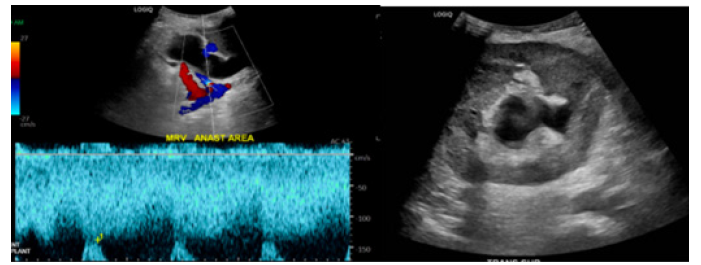

Computed Tomography (CT) upon admission demonstrated the transplanted ureter coursing into the right inguinal hernia resulting in obstruction with marked transplant hydroureteronephrosis (Figure 1). Both urine and blood cultures were found to be positive for Proteus mirabilis for which he was subsequently treated. Ultrasound of the transplanted kidney the following day continued to demonstrate hydroureteronephrosis with no change from prior CT. Fortunately, transplant vasculature was found to be patent with only mild tapered narrowing at the donor renal vein anastomosis (Figure 2). Interventional radiology was consulted for the placement of a percutaneous nephroureteral catheter that was successfully placed on hospital day 1.

Figure 1: CT imaging demonstrating obstruction of the ureter secondary to incarcerated right inguinal hernia.